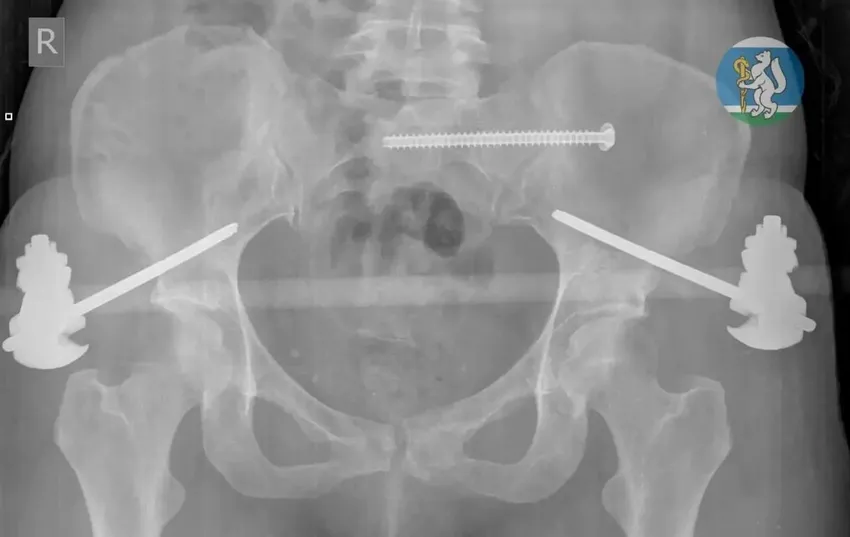

Пострадавшая, как стало известно, выпала из окна, поскользнувшись на подоконнике, когда мыла окна. Каким-то чудом женщина пережила падение, но получила серьезные травмы. Ее увезли в больницу с черепно-мозговой травмой, повреждением позвоночника, переломами таза и ноги.

Медикам удалось реанимировать пострадавшую, а затем они успешно провели несколько операций, «починив» переломанные ноги и таз. В течение месяца екатеринбурженка лежала в больнице, восстанавливаясь, а затем ее выписали домой. Теперь ей предстоит пройти долгую реабилитацию и вернуться к полноценной жизни.